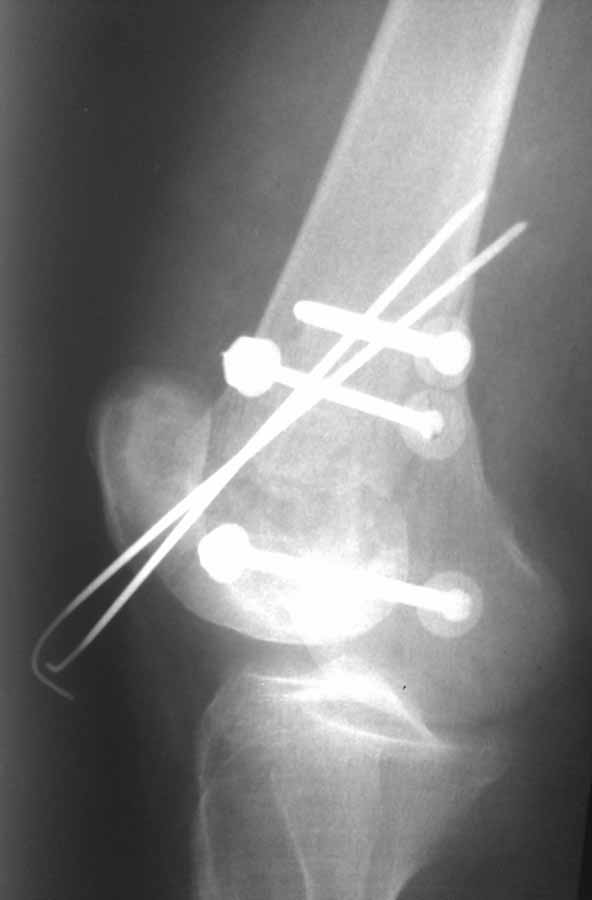

Коллеги, извиняюсь за задержку с результатом. Через медиальную артротомию обнажили н/3 бедра, отрепонировали внутренний мыщелок, затем по нему сопоставили суставную поверхность бедра с латеральным мыщелком.

По прямому снимку репозиция удалось, поздравляю! А с латеральной стороны подозрение на флексионный компонент латерального мыщелка остается, а снимок получился косым, надо было бы повторить.

Выбор имплантов не совсем удачный, подкожно выступающие болты в мыщелках вскоре могут привести к проблемам. Вместо солитарной фиксации болтом-стяжкой дистально можно было бы добавить пару винтов, которые создали бы ротационную стабильность и межфрагментарную компрессию.

Возможно, есть скрытый замысел, неочевидный для нас - не понятны латерально оставленные спицы. Спицы возможный очаг вторичного осложнения, и, тем более у взрослых, тонкие спицы не создают адекватную фиксацию.

Djoldas,скрытого смысла в спицах нет. Без них латеральный мыщелок получается фиксированным только к медиальному, который, в свою очередь, фиксирован к проксимальному отломку. Соответственно латеральный мыщелок не фиксирован к бедру. Спицами мы попытались создать какую-никакую-стабильность латерального мыщелка относительно проксимального отломка бедра.

Болт-стяжка, на мой взгляд, создает не меньшую межфрагментарную компрессию чем винты. Не понял относительно ротационной стабильности винтов.